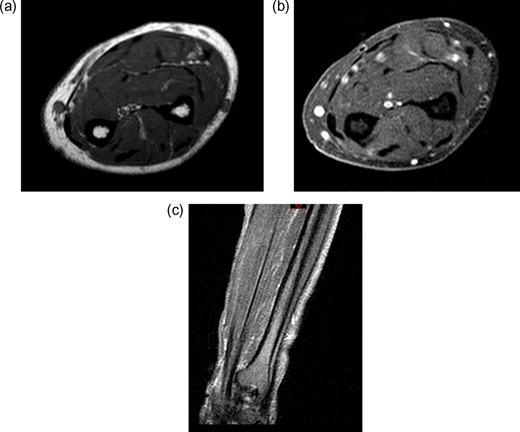

A 71-year-old male was referred to sarcoma clinic on 11/9/2017 with a painless swelling in his right forearm. He had a previous history of primary retro-peritoneal leiomyosarcoma surgery in 2011 with subsequent liver and lung metastases for which he underwent surgical resection in January 2017. His other past medical history included benign prostatic hypertrophy (controlled with medication), otherwise he was fully mobile, fit and well. This right-hand dominant male described a gradual 3-month history of increasing painless swelling to the volar aspect of the right forearm with full function of the arm and no neurological deficit. On clinical examination, there was a soft 5 × 4 cm swelling, 5 cm proximal to wrist crease in the volar compartment of the right forearm. The swelling was fixed, non-tender with no distal neurovascular deficit and or regional lymphadenopathy. Magnetic resonance imaging (MRI) of the right forearm demonstrated a 45 × 33 × 19 mm mass in the volar aspect in close relation to the median nerve (Fig. 1). Ultrasound-guided needle core biopsy was consistent with LMS and the histology was similar to the previous LMS suggesting the possibility of metastatic LMS. Staging studies did not show any other metastatic deposits. Following multidisciplinary team discussion, he underwent planned marginal excision of the metastatic sarcoma with preservation of the median nerve. Histology confirmed LMS composed of spindle cells with eosinophilic cytoplasm with mild pleomorphism confined within the perimysium with no necrosis or vascular invasion (trojani grade 1). The patient recovered well post operatively with no neurological deficit only complicated with a mild episode of cellulitis to the wound site which fully resolved with a short course of oral antibiotics. One year after surgery, the patient has full function and use of his right hand and there is no evidence of LMS recurrence or further metastatic spread both clinically and radiologically on recent CT scan of his chest, abdomen and pelvis and MRI scan of the forearm (Fig. 2).

Pre-treatment contrast MRI of forearm showing large soft-tissue mas lesion involving the flexor aspect of right forearm (a) axial T2, (b) coronal T2, (c) axial T1 and (d) coronal T1.